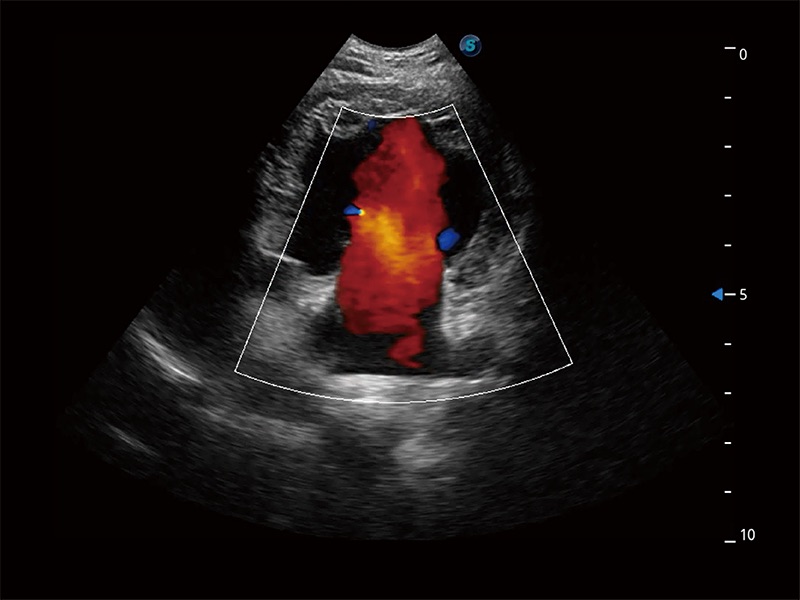

ProPet 80 配备了丰富的心脏探头群、先进的成像技术和专业的心脏测量工具,可帮助动物医生为不同体型和生理结构的动物提供心脏和心肌功能的全面评估。

实时用颜色表示心肌组织运动,观察和定量组织的运动情況,对快速检测与评估心肌的灌注和活性、电传导及心肌收缩和舒张功能等均能提供重要的诊断信息。

通过心肌识别技术与二维斑点追踪技术相结合,对心脏的超声图像进行量化分析。计算心肌17个节段的应变、应变率、速度、位移等,并通过牛眼图的形式进行呈现。

通过360度任意调节3条M型取样线,在同一心动周期上观察心脏不同位置的运动曲线,得到准确的心功能测量数据,有效评估心肌运动及左心室功能。

能够增加心肌组织与血流之间的区别。对于心脏扫查困难的动物,可提供更好的心内膜边界的显示。

能够基于左心室壁追踪和辛普森法,自动计算射血分数,支持多个可移动点描迹,与手动测量相比,极大节省了动物医生的时间和精力。